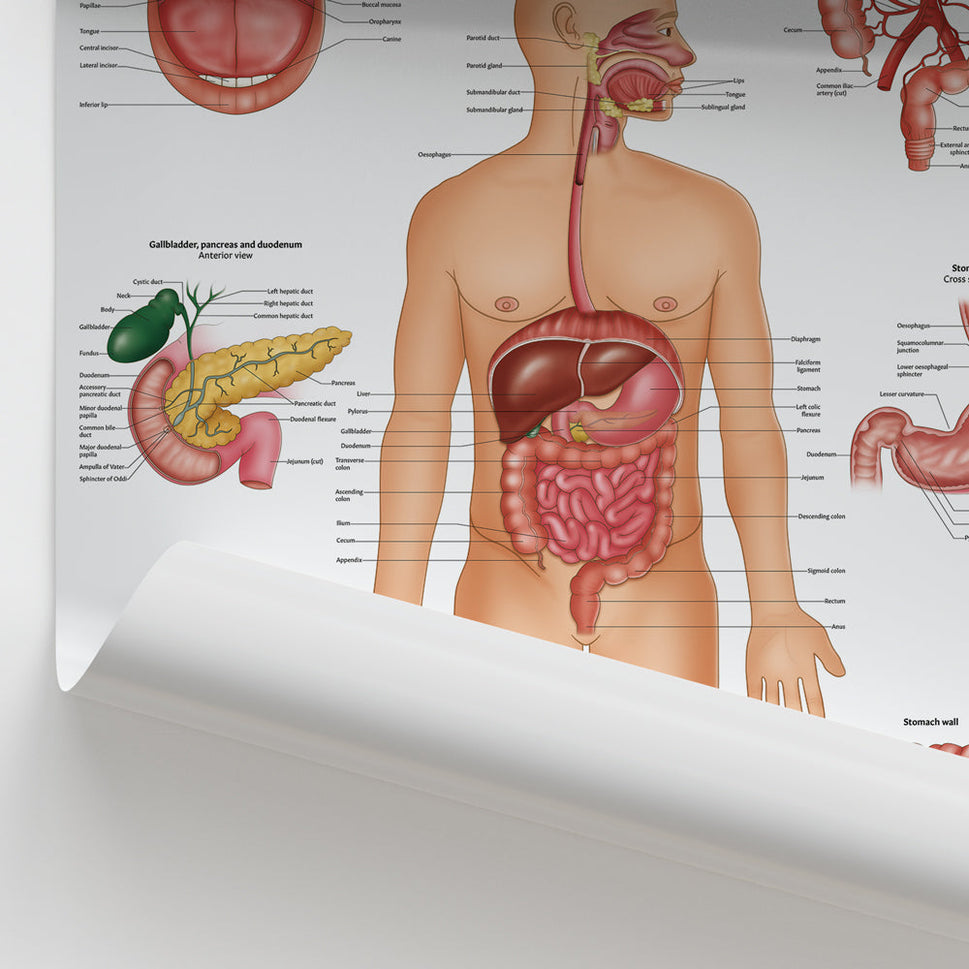

Enhance medical education with our collection of digestive system anatomical models including the stomach, liver, gallbladder, pancreas & colon models. Discover the anatomy of healthy organs as well as common gastrointestinal diseases such as stomach ulcers, gallstones and liver cirrhosis. Our digestive system anatomy posters are ideal for study and patient education.

At AnatomyStuff we stock a diverse range of digestive system anatomical models to suit your training needs. From budget models and affordable medical education posters to highly advanced 3D printed bowel models, you can transform medical training and patient education. As well as our own exclusive collection, we are proud resellers of 3B Scientific, Anatomy Lab, Denoyer-Geppert Science Company, ESP Models, Erler Zimmer and GPI Anatomicals. Explore our exclusive collection of digestive system anatomy charts, posters, fine art prints and digital anatomy study guides. Discover the anatomy of key organs like the liver, stomach, pancreas and bowel as well as the pathophysiology of common conditions like peptic ulcer disease, coeliac disease, IBD and much more. We have anatomy posters suitable for school children all the way up to medical degree level. From a liver anatomy poster to a digital study guide all about common GI disorders, find exactly what you need right here to enhance medical training and patient education.